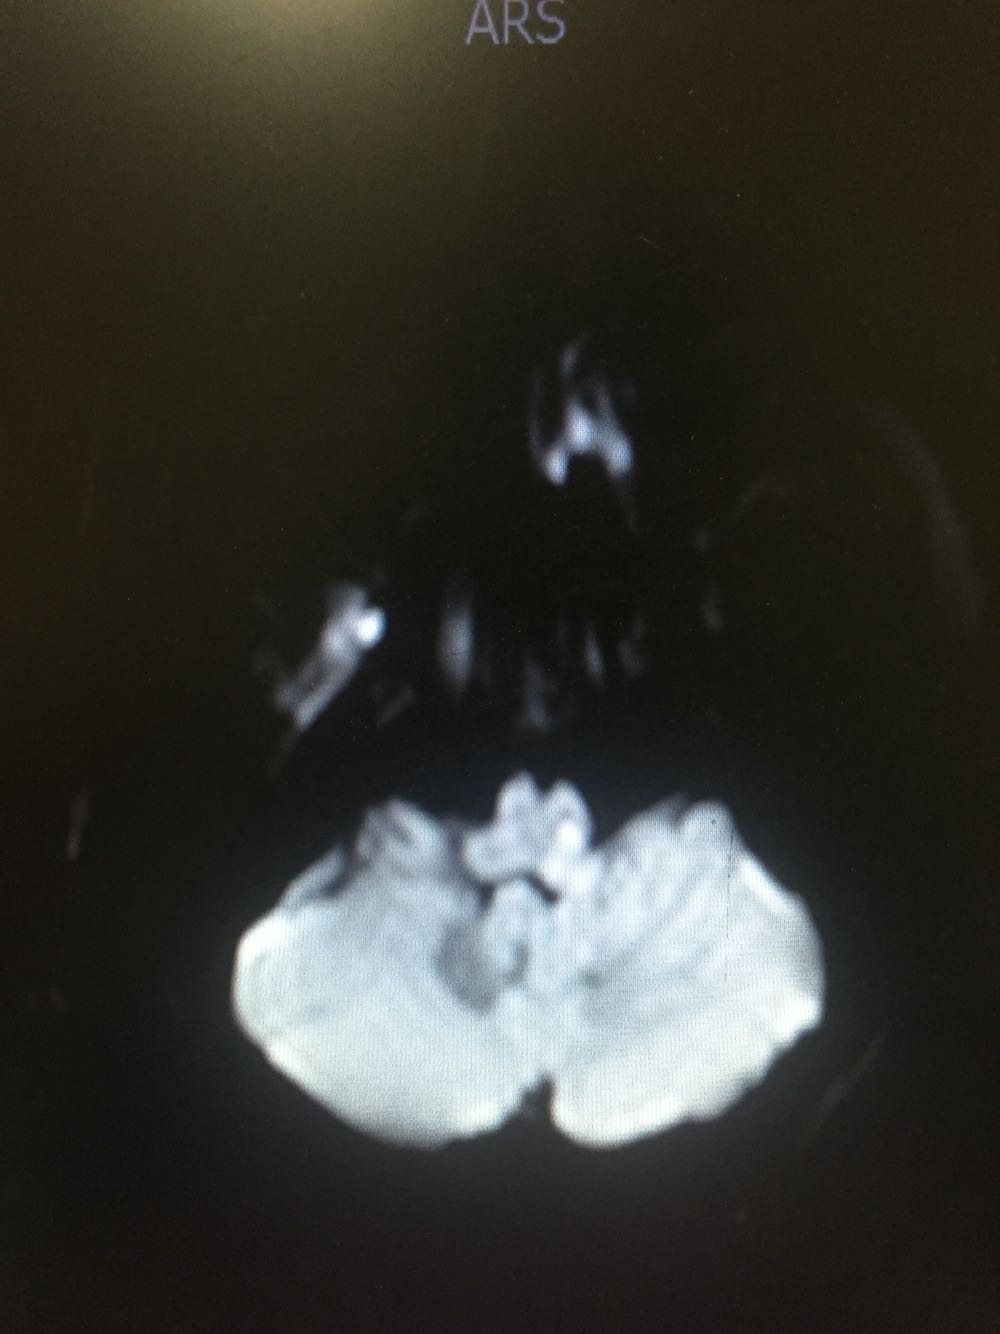

延髓梗死

延髓梗死、高血压、高脂血症 治疗改善循环、抗血小板聚集、脑保护、营养神经、调控血压、血脂对症治疗